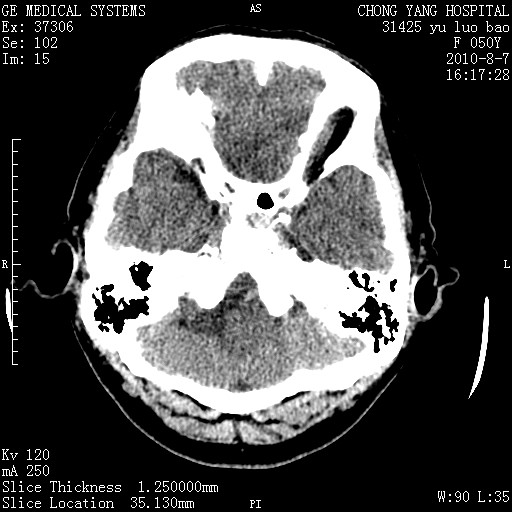

标题: CT28285:听力下降一年,头昏。 [打印本页]

标题: CT28285:听力下降一年,头昏。

右侧桥小脑角去等密度占位,右侧内听道扩大、骨质吸收,考虑:右侧听神经瘤,建议增强检查。

右侧内听道扩大、骨质吸收,中脑受压左移,考虑:右侧听神经瘤,建议增强检查。支持!

骨窗示右侧内听道扩大,考虑右侧听神经瘤。

右侧桥小脑角区等密度占位,内耳道扩大,听神经瘤